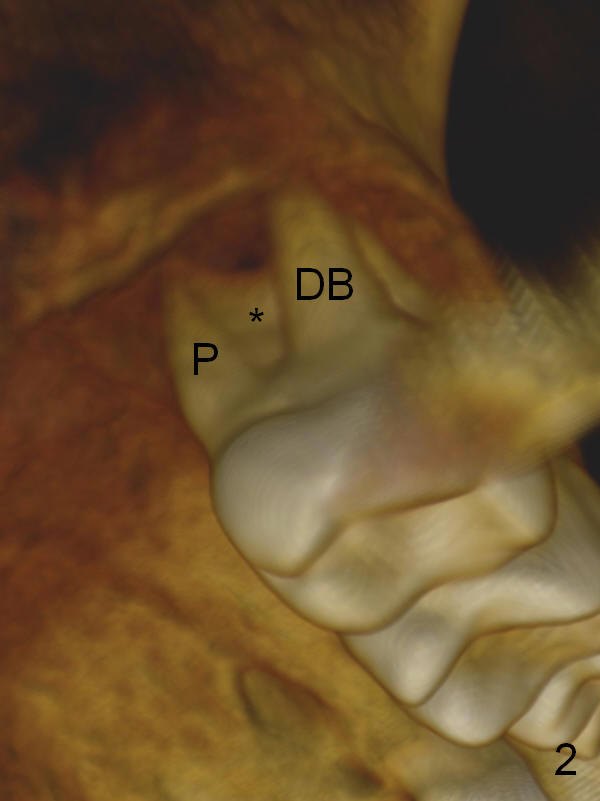

A 46-year-old lady is a typical dental phobic, but she is reasonable. Her chronic periodontitis is generalized and severe (Fig.1 3-D image, taken 1 year ago). An implant has been placed at #6 (healed site). It fails for the first time, probably due to bone loss after extraction. Soon after last periodontal maintenance, the tooth #2 develops pain and swelling. Immediate implant is a must.

The socket is wider buccopalatally (Fig.2 (3-D disto-occlusal view),3 (coronal section)) than mesiodistally (Fig.1,4 (sagittal section),5 (axial section)). Unless more bone loss has occurred in the last year, a 6x10 mm UF implant is to be placed in the middle of the socket (Fig.6, (soaked with 2% Xylocaine/1:50,000 Epinephrine gauze)) with bone graft to be placed in the buccal and palatal gaps (red circles). Bone density in the middle of the socket is 550-700 Hounsfield units. Use RT2 or 2 mm pilot drill to start osteotomy ~ 3 mm. The largest osteotome is RT4, or largest reamer 4 mm, followed by 4.5x17 mm tap at 14 mm, until 6x17 mm one. Make sure that the sinus floor is penetrated.